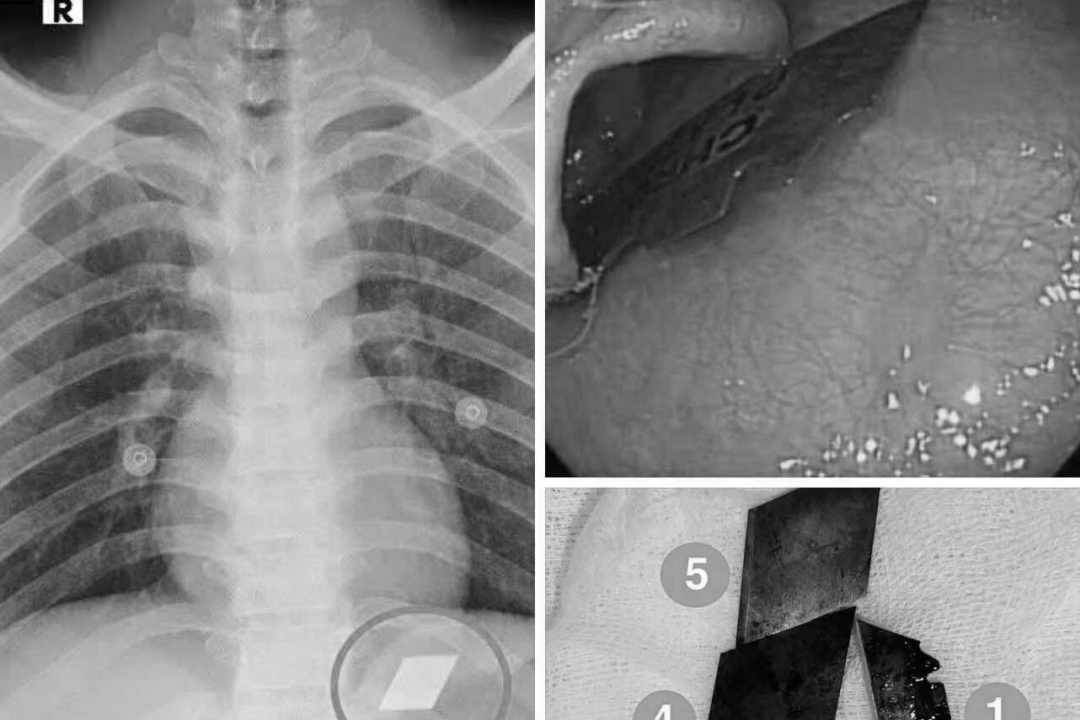

Ngày 10/7, Khoa Hồi sức cấp cứu của Bệnh viện Đa khoa Bình Dương đã tiếp nhận một trường hợp cấp cứu hiếm gặp và phức tạp. Bệnh nhân P.V.L, 26 tuổi, được đưa vào viện sau khi nuốt nhiều dị vật kim loại sắc nhọn, bao gồm dao rọc giấy và dao lam. Ngay sau khi tiếp nhận, các bác sĩ đã tiến hành thăm khám và chụp X-quang để xác định vị trí của các dị vật.

Qua thăm khám và chụp X-quang, các bác sĩ phát hiện các dị vật cản quang tại vị trí dạ dày. Bệnh nhân ngay lập tức được chỉ định nội soi cấp cứu để gắp bỏ dị vật. Quá trình nội soi được thực hiện dưới sự phối hợp chặt chẽ giữa ê-kíp nội soi và gây mê, nhằm đảm bảo an toàn và hiệu quả.

Sau một thời gian ngắn thực hiện thủ thuật, các bác sĩ đã thành công gắp 4 lưỡi dao rọc giấy ra khỏi dạ dày và một phần lưỡi dao lam mắc tại vùng hạ họng – miệng thực quản. Sau thủ thuật, bệnh nhân được theo dõi sát và đã ổn định sức khỏe, xuất viện trong tình trạng an toàn.